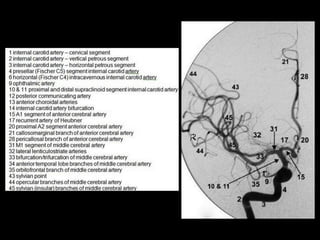

-Frontal view of the anterior (carotid) intracranial

circulation

1 internal carotid artery - cervical segment

2 internal carotid artery - vertical petrous segment

3 internal carotid artery – horizontal petrous

segment

4 presellar segment (C5) internal carotid artery

9 ophthalmic artery

10 and 11 supraclinoid segment internal carotid

artery

13 anterior choroidal artery

14 internal carotid artery bifurcation

15 A1 segment of anterior cerebral artery

16 medial lenticulostriate arteries

17 recurrent artery of Heubner

18 A1-A2 junction anterior cerebral artery

19 anterior communicating artery

20 proximal A2 segment anterior cerebral artery

21 callosomarginal branch of anterior cerebral

28 pericallosal branch of anterior cerebral artery

31 M1 segment of middle cerebral artery

32 lateral lenticulostriate arteries

33 bifurcation/trifurcation of middle cerebral

34 anterior temporal lobe branches of middle

cerebral

43 sylvian point

44 opercular branches of middle cerebral artery

45 sylvian(insular) branches of middle cerebral